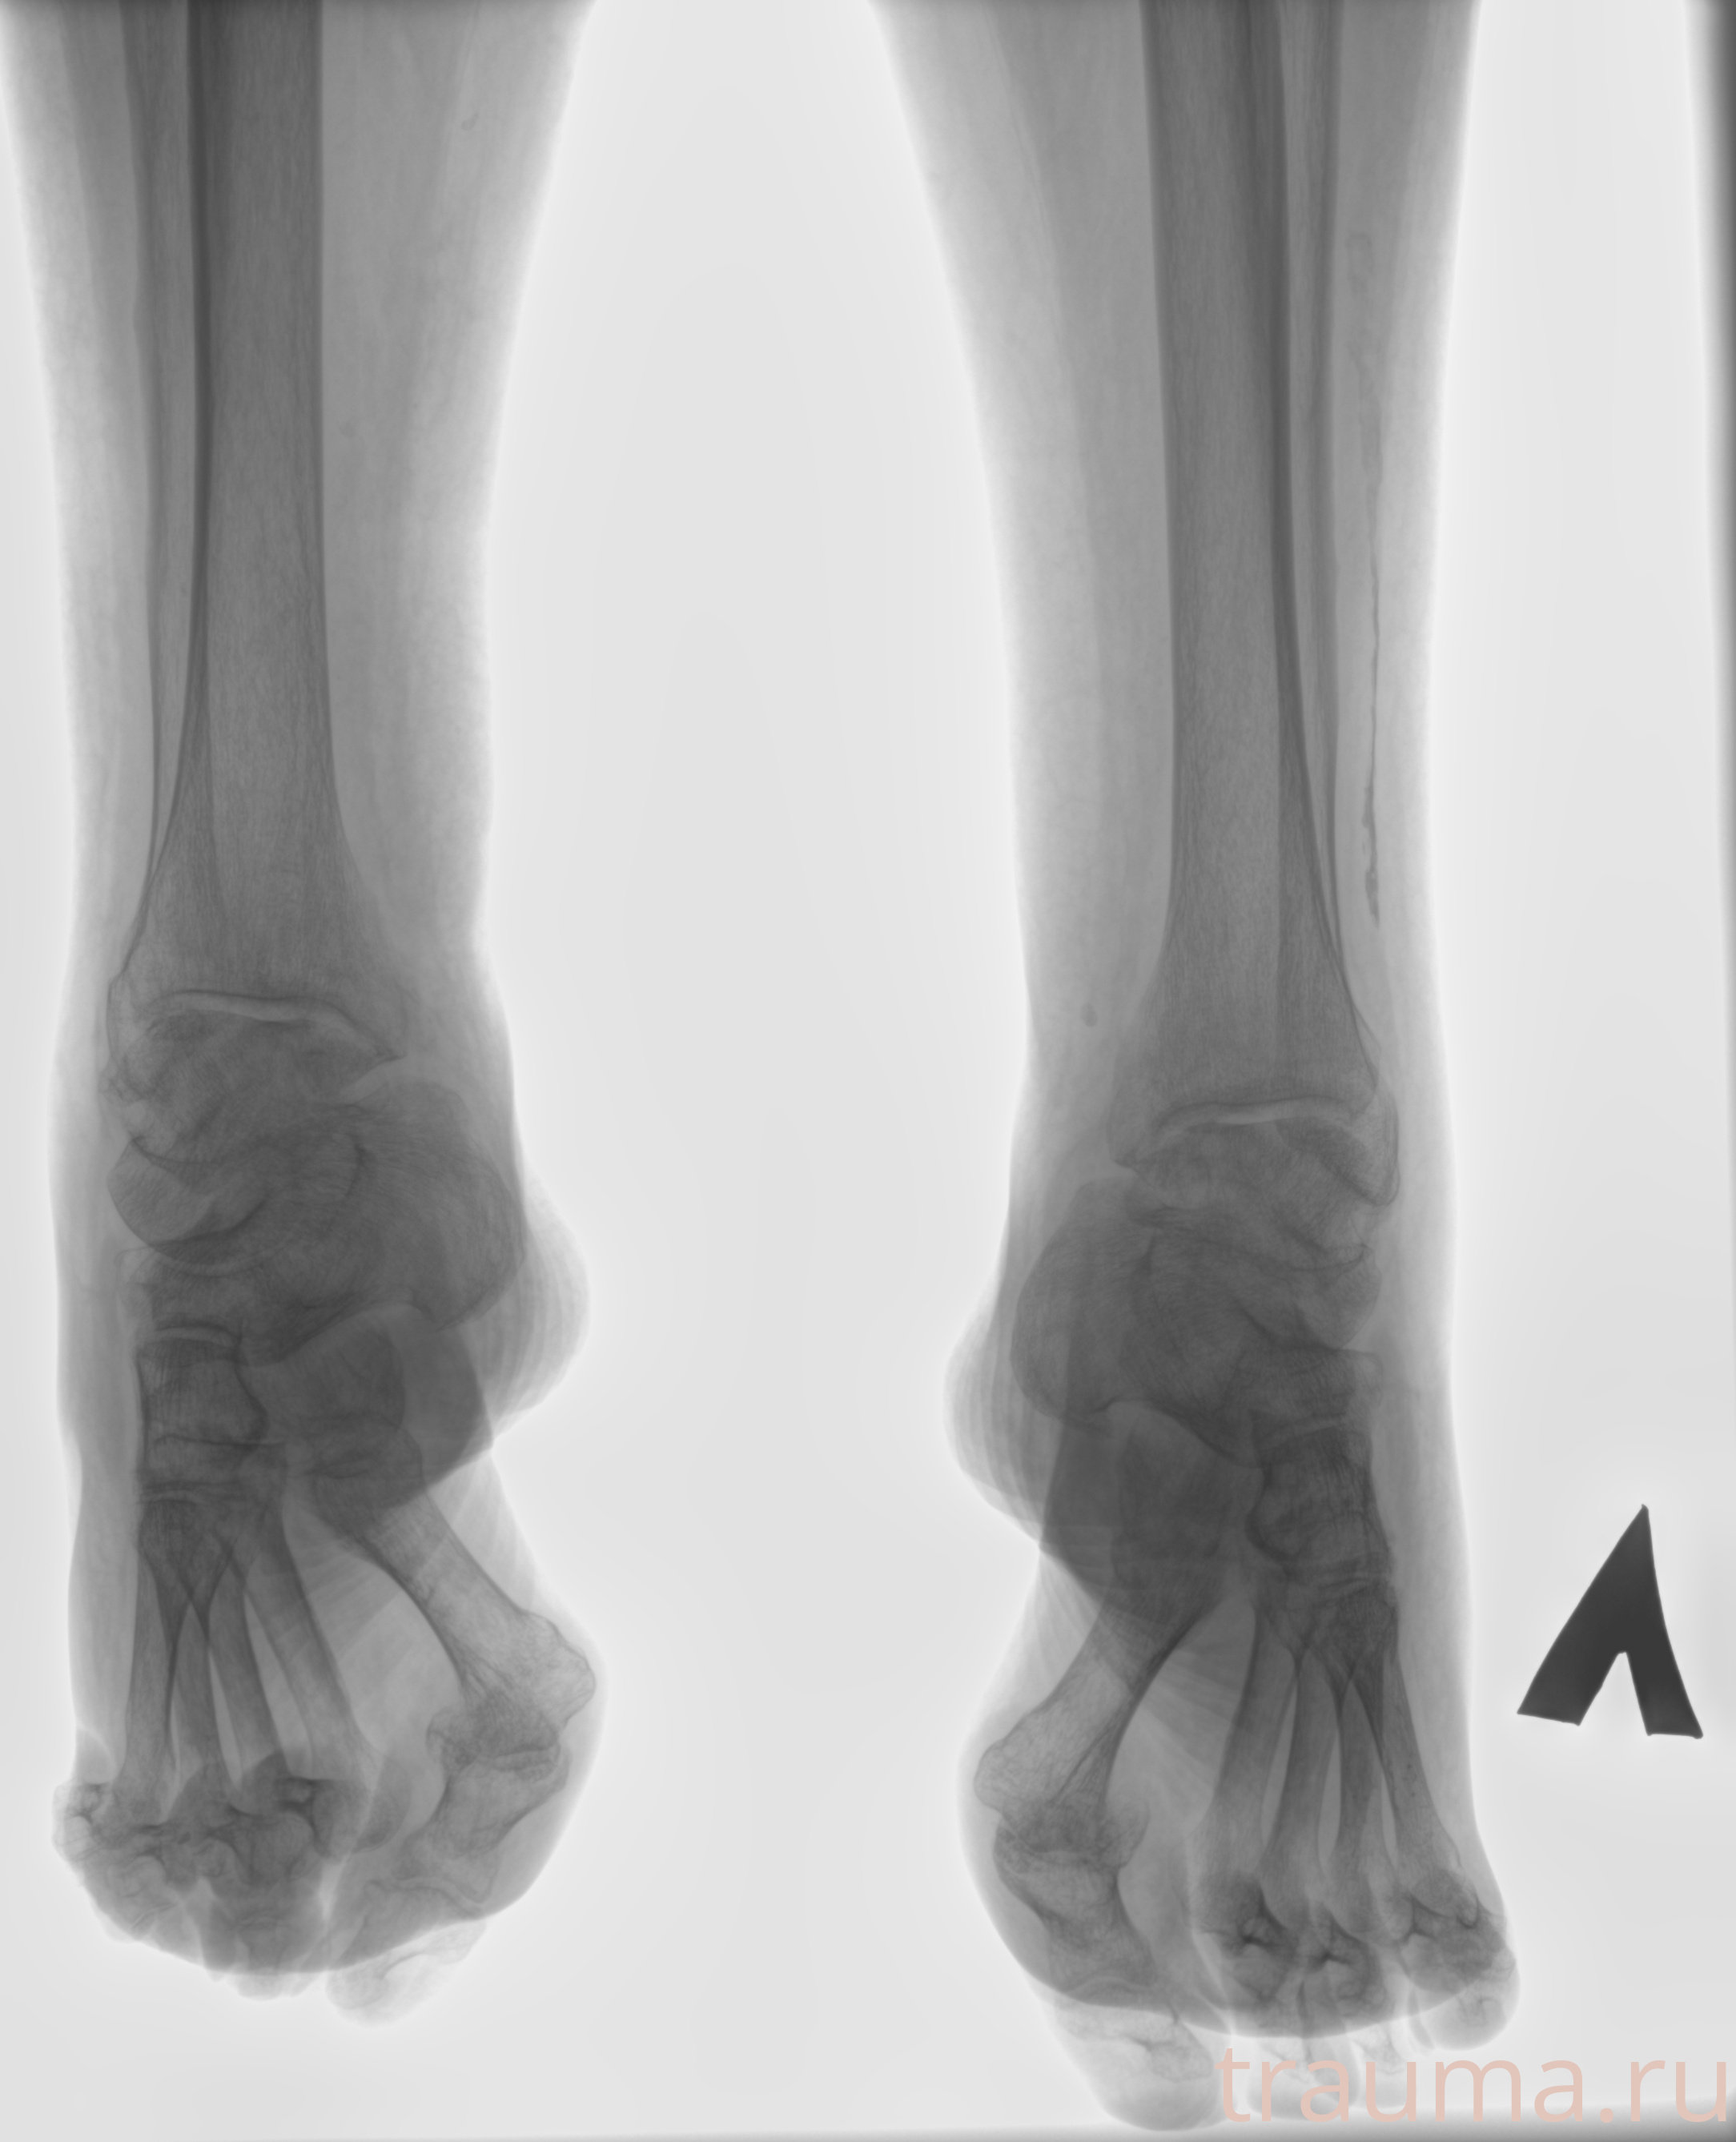

Рентген на дому: по вашему адресу приезжает врач-рентгенолог, травматолог-ортопед с мобильным рентгеновским аппаратом, проводит диагностику травмы или заболевания, делает необходимые рентгенограммы, дает рекомендации по дальнейшему лечению. Получить качественные снимки в домашних условиях возможно благодаря уникальной методике, разработанной МосРентген Центром для института  Склифосовского